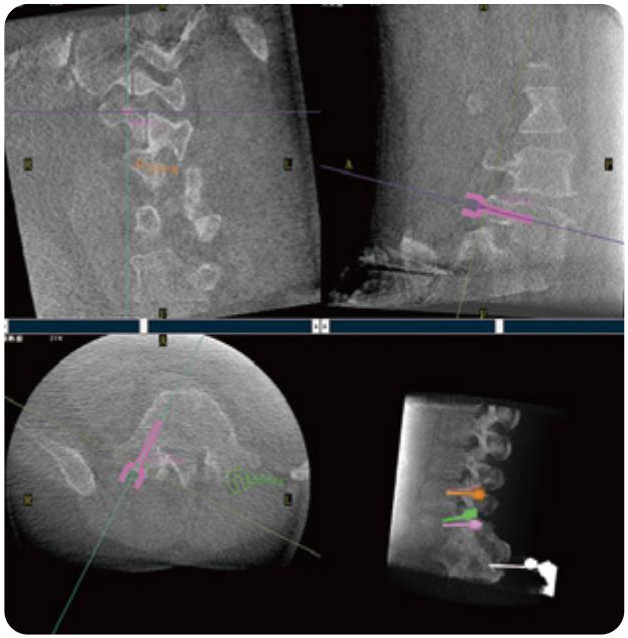

PL300B可應用于多節段脊柱外科手術(shù),輔助醫生定位病灶部位,為脊柱外科手術(shù)(經(jīng)皮椎體成形術(shù)、椎弓根螺釘內固定術(shù)等術(shù)式)提供術(shù)前手術(shù)流程規劃、入釘位置、角度可視化引導,模擬仿真入釘輔助。

PL300B搭配普愛(ài)醫療自主研發(fā)生產(chǎn)的平板3D C形臂,借助一體化自適應配準( 軌跡配準)技術(shù),通過(guò)追蹤C形臂三維采集軌跡,自動(dòng)完成圖像坐標建立和系統坐標配準。配準精度更高,操作步驟少,系統運作效率高。